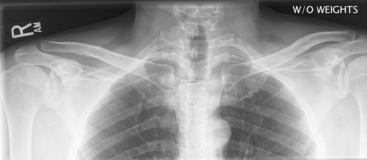

(AP—Bilateral with and without Weights)

Warning: Rule out fracture first before taking “with weight” projection.

• 35 × 43 cm C.W. (14 × 17″) or (2) 18 × 24 cm (8 × 10″) for broad shoulders